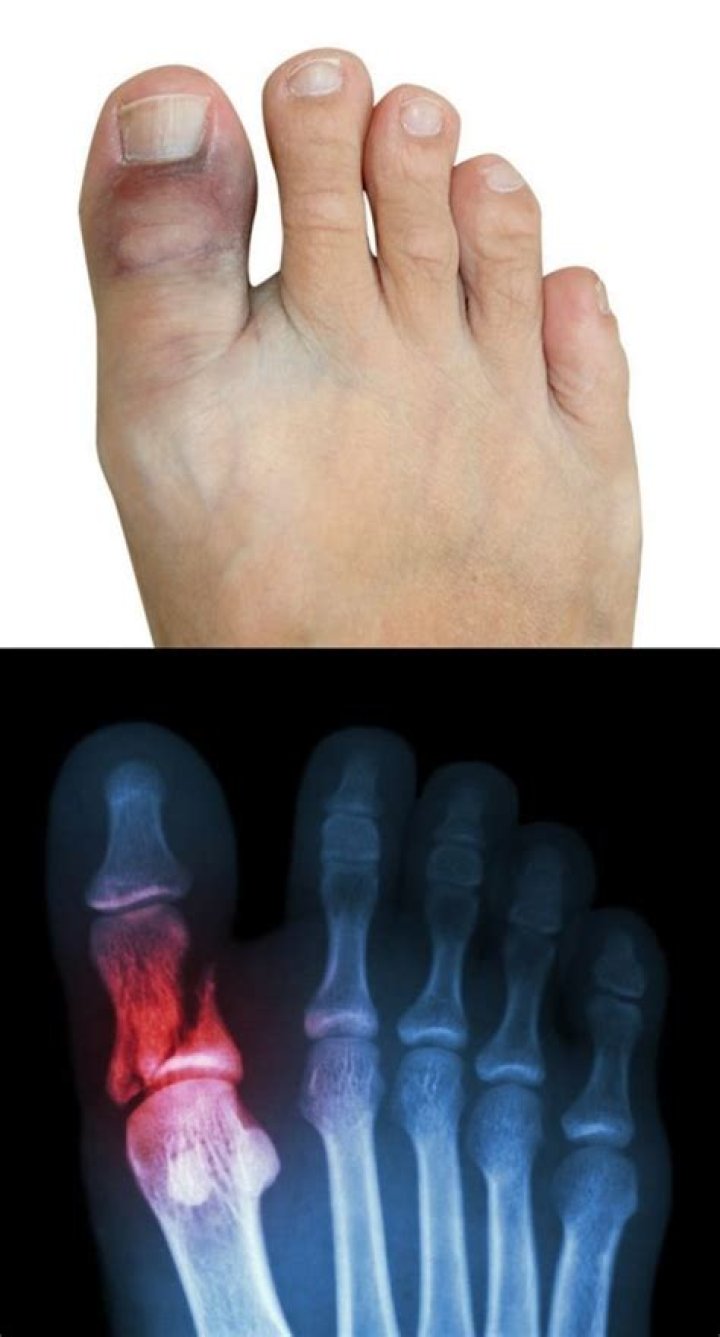

What does a sprained toe look like?

A sprained toe shouldn't look dislocated. It will still swell, but will likely have less bruising. A sprained toe may be painful for several days, but should then begin to improve. One other key difference between a break and a sprain is the location of the pain.

What's a broken toe look like?

Broken Toe Symptoms

Bruising of the skin around the toe may also be noticeable. The toe may not look normal, and it may even look bent or deformed if the broken bone is out of place. It may be difficult to walk because of the pain, especially if the big toe is fractured. Shoes may be painful to wear or feel too tight.

While sprained toes usually still can be moved and flexed (albeit with pain), broken toes usually won't move at all (or at least not very much). Broken toes are also more likely to cause numbness or tingling, more likely to cause bleeding, and more likely to cause “unusual” symptoms like disorientation or faintness.